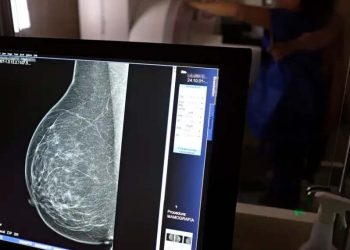

Geral Outubro Rosa | Mês é dedicado a conscientização sobre o câncer de mama e colo do útero 01/10/2020 2.5k